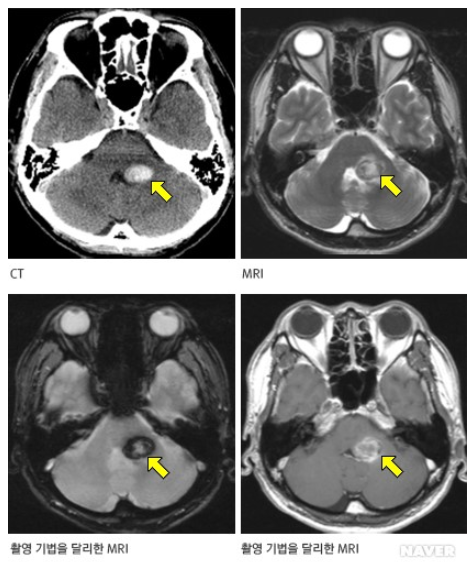

해면상혈관종은 뇌, 척수에서 모세혈관이 비정상적으로 팽창해 해면체 모양으로 뭉쳐진 종괴다. 시간에 따라 병변의 수가 증가하고 다발성 뇌출혈을 유발할 수도 있어 주의가 필요하다.

추가로 연구팀이 가족성 해면상혈관종의 발생 부위를 분석한 결과, 유전자변이 보유 환자는 ‘뇌간’ 부위에 병변이 발생하는 빈도가 확연히 높은 것으로 확인됐다.

즉 MRI 검사 시 뇌간 부위에서 해면상혈관종이 발견된 사람은 유전자변이 보유 가능성이 있으므로 특히 유전자검사를 권고한다고 연구팀은 강조했다.